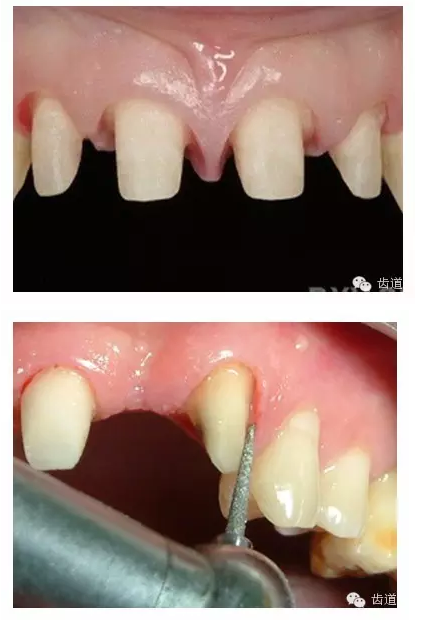

l保護(hù)牙體組織

l基牙具有良好的固位形

l基牙具有良好的抗力形

l預(yù)留修復(fù)體的空間

l邊緣的適合性

l保護(hù)牙周組織